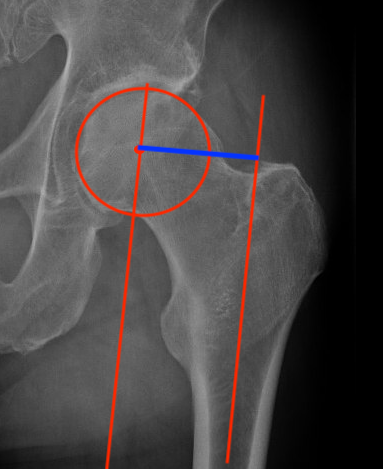

Femoral offset

- perpendicular distance

- from the centre of the femoral head

- to the long axis of the femur

Femoral offsetFemoral offset